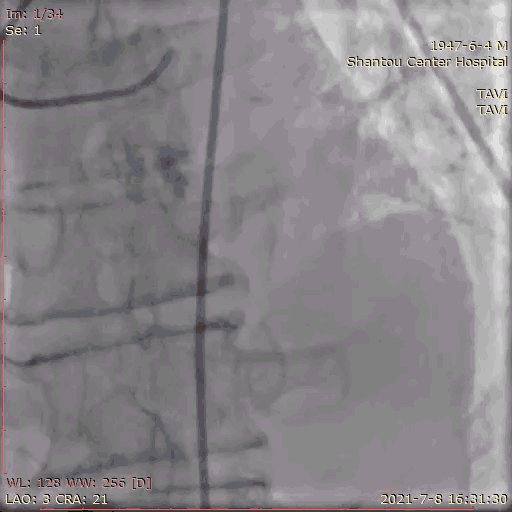

主动脉根部造影

临时起搏器植入后,辅入路穿刺,猪尾导管置于无冠窦底进行主动脉根部造影。

初步判断释放体位是否合适。

观察瓣叶活动度、是否合并反流,有利于跨瓣。

左右冠通畅,存在一定反流,有一定耐受能力,球扩时,循环崩溃风险较小。

左冠窦瓣叶活动度高、无钙化,无冠窦右冠窦活动度减轻,且钙化集中在基底部,右冠风险较左冠低。